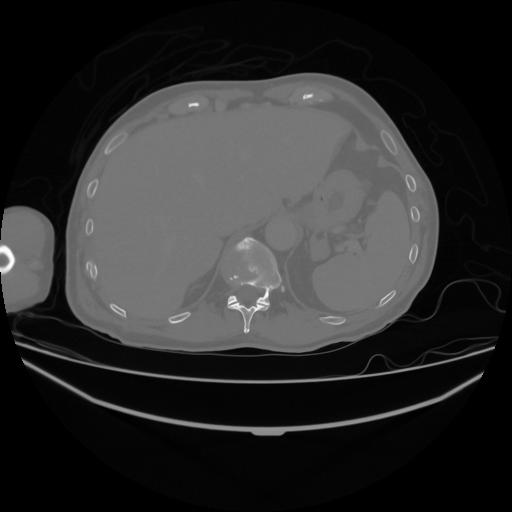

5 CUERPO,CE,Vol,1.0,CUERPO,,